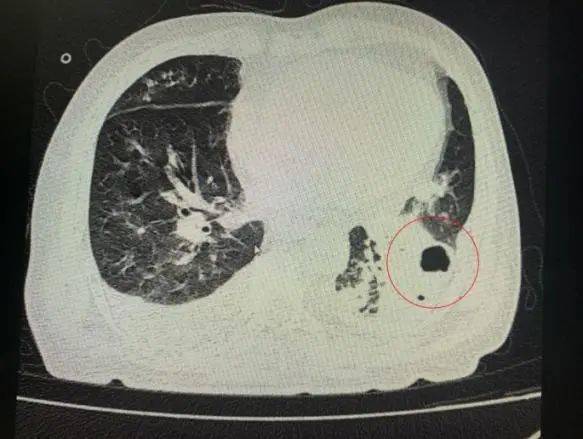

番禺院区呼吸内科何梦璋主任接诊后 , 对钟叔进行详细检查 。 此时 , 钟叔的病情已经十分危急 , 由于不能自主呼吸 , 他带上了无创呼吸机辅助呼吸治疗 。 看到钟叔胸片时 , 医护人员头皮也一阵发麻 , 胸部CT可见双肺多发的炎症浸润、双肺多发空洞 。 通俗来说 , 钟叔的肺部已经被病原体蚕食 , 啃出无数个大小各异的洞!可怕的是 , 这种病变对肺功能的破坏是永久性、不可恢复的 。 根据钟叔病史以及胸部CT结果 , 最终诊断为“吸入性肺脓肿” 。

钟叔的肺部被病原体蚕食 , 啃出无数个大小各异的洞 。